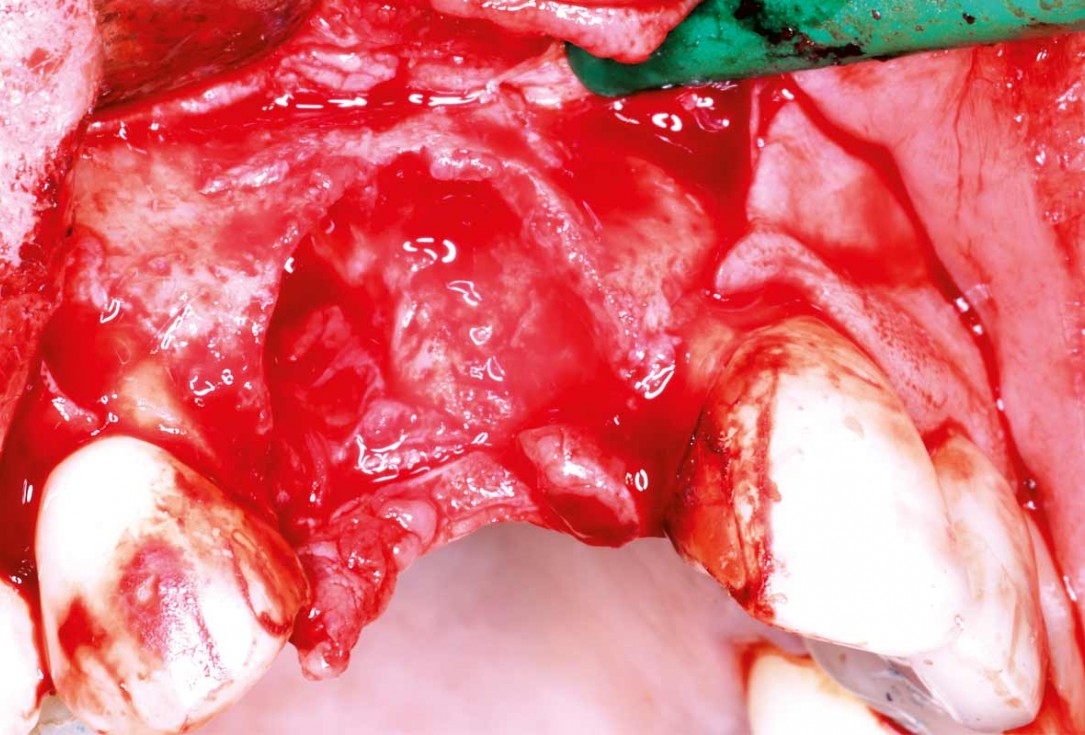

03/10 - Flap elevation, exposition of the defect which reach the apex of 12 and 11Maxillary bone reconstruction in the anterior area with cerabone® and Jason® membrane - Dr. P.-Y. Gegout & Prof. O. Huck

04/10 - Ridge defect after the extraction of 11 and 12Maxillary bone reconstruction in the anterior area with cerabone® and Jason® membrane - Dr. P.-Y. Gegout & Prof. O. Huck